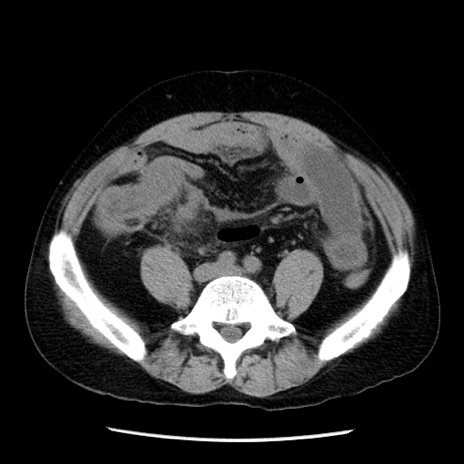

症例29(横断像)

【症例】40歳代男性

【現病歴】2日前から胃痛あり。徐々に周期的な激痛に変化した。本日になっても激痛があるため受診。

【身体所見】意識清明、BT 38-39℃台あり、腹部:膨満、やや硬、右下腹部に圧痛あり。

【データ】WBC 8500、CRP 23.26